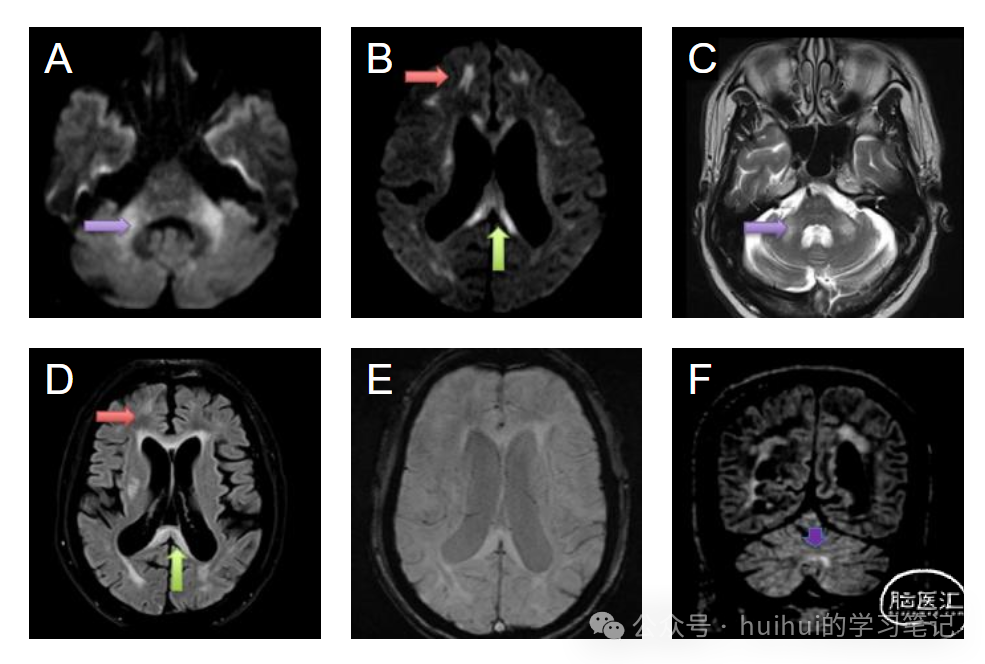

● FXTAS最常见的特征是MCP征(小脑中脚T2高信号),见于60%的男性患者和13%的女性患者。

● 第二个主要影像学特征是胼胝体压部T2高信号,与MCP征一样常见,也更常见于男性。FLAIR高信号可见于小脑的椎旁区域。

● 其他影像学特征:脑桥、岛叶、脑室周围白质T2高信号,弥漫性脑和小脑萎缩,小脑上、中脚、大脑脚、穹窿、终纹各向异性分数明显降低。